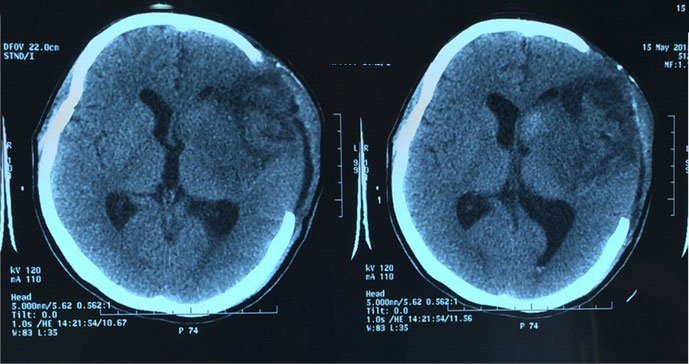

Phù não là tình trạng xảy ra khi dịch tích tụ xung quanh tổ chức não, gây gia tăng áp lực nội sọ. Phù não hay còn được gọi cách khác dưới cái tên biến chứng mà nó gây ra là tăng áp lực nội sọ.

Phù não là một bệnh lý có thể xuất hiện ở những vị trí đặc biệt của não hoặc bị phù toàn bộ não. Tình trạng này sẽ tùy thuộc vào những nguyên nhân gây bệnh. Phù não sẽ tạo ra những áp lực lớn ở bên trong hộp sọ, khiến cho quá trình cung cấp máu lên não bị hạn chế. Các áp lực có thể sẽ bị gia tăng và gây chèn ép các mạch máu nuôi não và làm cho máu không lên được bộ não. Từ đó, nguồn cung oxy cho những tế bào não cũng sẽ bị hạn chế.

Tình trạng thiếu oxy có thể khiến cho các tế bào não bị tổn thương vô cùng nghiêm trọng. Nguy hiểm hơn là có thể gây chết não. Bên cạnh đó, tình trạng não bị phù cũng làm cho quá trình lưu thông các dịch não tủy bị gián đoạn và khiến cho não phù thêm nghiêm trọng hơn.